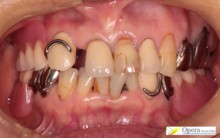

入歯装着

入れ歯を入れたところです。

装着日の診療時間は5分でした。痛みなく、スポッと入りました。

1週間後の調整時間は10分でした。 ちょっと痛むところがあるというので、その場所を削りました。

その後は問題なく使えているとのことです。